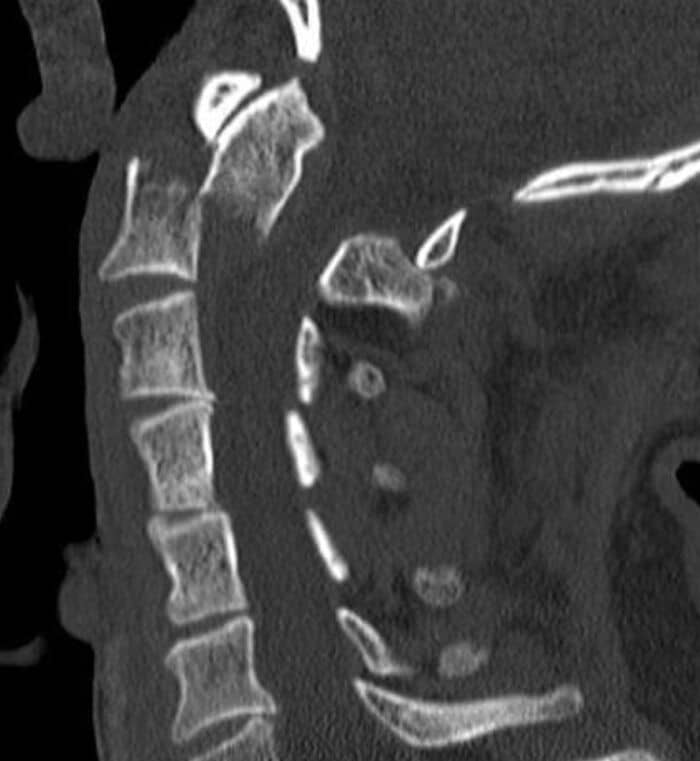

Not a doctor, but a 3rd year med student. During my neurosurgery clerkship this year, a patient came into the ER after being hit by a car. While looking at the head and neck CT, one of the residents said “holy s**t y’all come look at this.” The patient’s dens of his C2 vertebra (axis) had jumped under and to the front of his C1 vertebra (atlas). Basically the guy was internally decapitated and any sudden neck movement could k**l him. Weird part is he had zero neurological deficits. No paralysis or loss of function. He should have been dead but lived with no lasting effects of the injury.